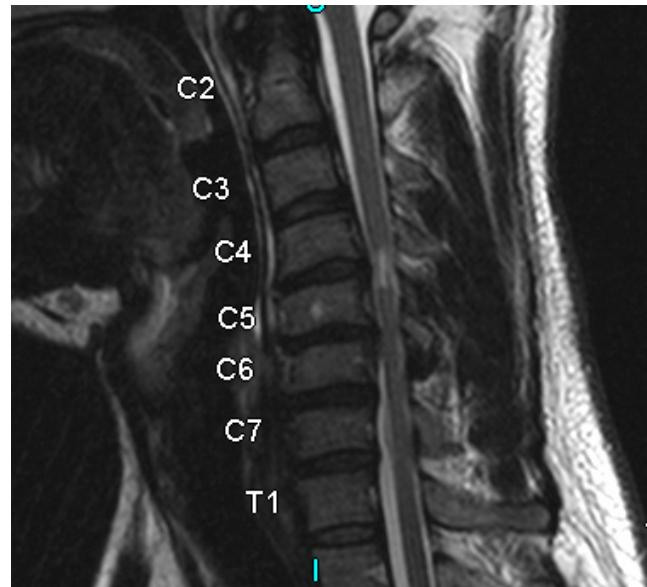

Cervical MyelopathyZ

- Definition: Common form of neurologic impairment caused by compression of cervical spinal cord, most commonly due to degenerative cervical spondylosis

- Typical presentation: Older patients with symmetric numbness and tingling in extremities, hand clumsiness, and gait imbalance

- Treatment: Usually surgical decompression and stabilization as condition is associated with step-wise progression

Imaging:

- MRI: Study of choice to evaluate degree of spinal cord and nerve root compression

Imaging Examples:

Surgical Treatment - Anterior Cervical Discectomy and Fusion: